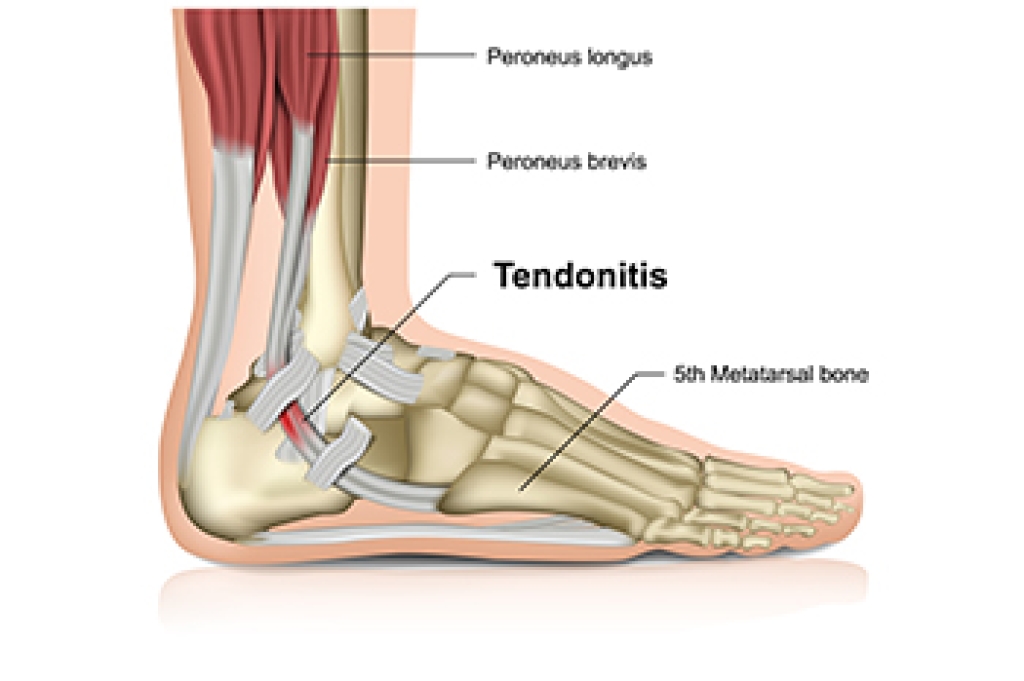

Achilles tendonitis, a common woe for runners, arises from inflammation in the strong tendon that connects the calf muscles to the heel bone. Typically linked to the runner's trifecta of too much, too fast, and too soon, recognizing symptoms of Achilles tendonitis is vital for timely intervention. These symptoms include initial stiffness that dissipates with warming up, in addition to pain and swelling near the heel. The runner may experience limited ankle flexibility during physical activities, and notice redness along the tendon. Other symptoms can include a distinct burning sensation, palpable scar tissue lumps, and an audible cracking or popping sound during ankle movement. Runners, constantly pushing their limits, are particularly prone to Achilles tendon injuries due to the repetitive stress involved in each stride. Speed and uphill training can increase the strain on the tendon. This can lead to overworking, tightening, and inflammation, which may result in Achilles tendonitis. If you are experiencing symptoms of Achilles tendonitis, it is suggested that you schedule an appointment with a podiatrist for a complete examination and treatment suggestions.

Achilles tendon injuries need immediate attention to avoid future complications. If you have any concerns, contact Edward Orman, DPM of Honeygo Podiatry. Our doctor can provide the care you need to keep you pain-free and on your feet.

What Is the Achilles Tendon?

The Achilles tendon is a tendon that connects the lower leg muscles and calf to the heel of the foot. It is the strongest tendon in the human body and is essential for making movement possible. Because this tendon is such an integral part of the body, any injuries to it can create immense difficulties and should immediately be presented to a doctor.

What Are the Symptoms of an Achilles Tendon Injury?

There are various types of injuries that can affect the Achilles tendon. The two most common injuries are Achilles tendinitis and ruptures of the tendon.

Achilles Tendinitis Symptoms

- Inflammation

- Dull to severe pain

- Increased blood flow to the tendon

- Thickening of the tendon

Rupture Symptoms

- Extreme pain and swelling in the foot

- Total immobility

Treatment and Prevention

Achilles tendon injuries are diagnosed by a thorough physical evaluation, which can include an MRI. Treatment involves rest, physical therapy, and in some cases, surgery. However, various preventative measures can be taken to avoid these injuries, such as:

- Thorough stretching of the tendon before and after exercise

- Strengthening exercises like calf raises, squats, leg curls, leg extensions, leg raises, lunges, and leg presses

If you have any questions please feel free to contact our offices located in Perry Hall, and Fallston, MD . We offer the newest diagnostic tools and technology to treat your foot and ankle needs.